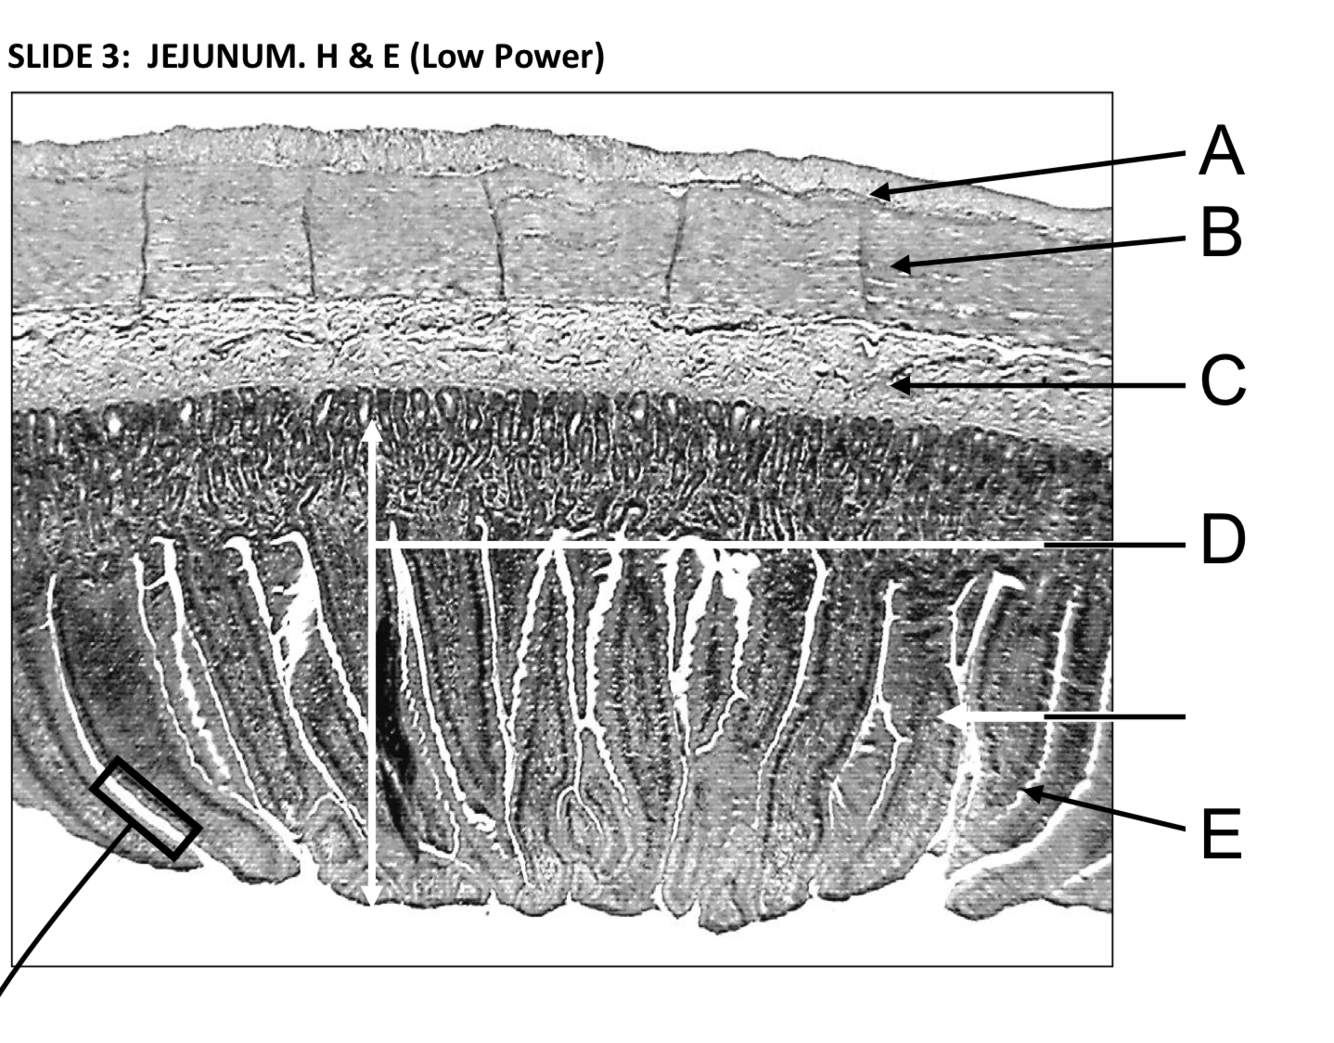

A - Longitudinal muscle layer

B - Circular muscle layer

C - Submucosa - loose connective tissue under a mucous membrane

D - Region of epithelium and subtending lamina propria (loose connective tissue)

E - Intestinal villi - increase the jejunal surface area. An examination of the edge of a villus at high power reveals the simple columar epithelium